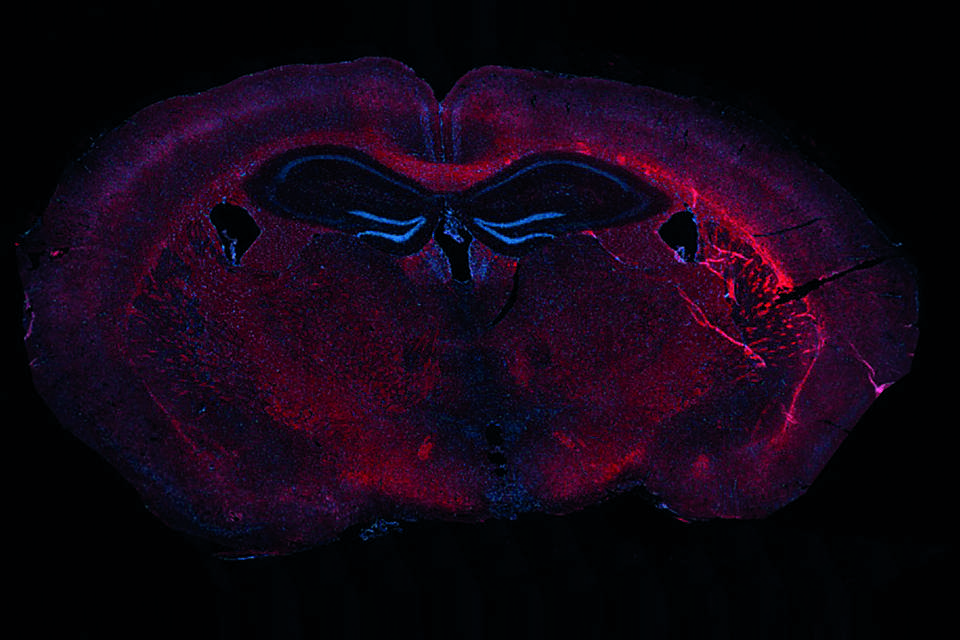

Molecular read-outs: Myelin visualisation (Luxol Fast Bleu staining), myelin layer thickness (TEM G-ratio), gene expression (qPCR), protein expression of myelin protein (MBP)

(example published as Houben et al. PNAS 2020; 117:5028-5038)

Representative images of LFB staining in the corpus callosum (around bregma −1.82 mm).

Representative TEM images and quantification of the G ratio in the corpus callosum)